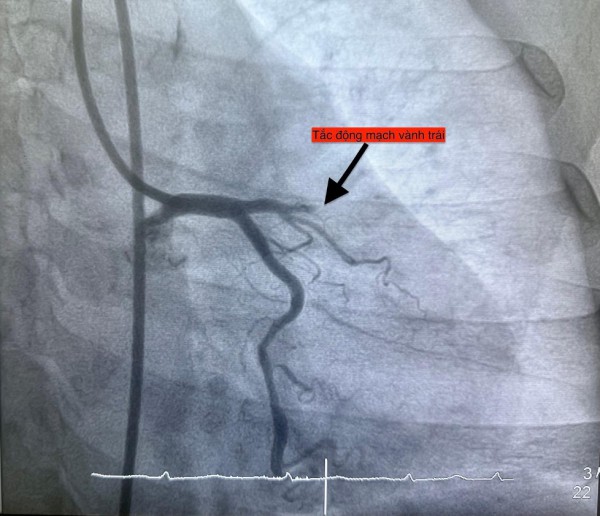

Trường hợp thứ tư, lúc 22 giờ 6 phút, nữ bệnh nhân 61 tuổi nhập viện vì đau ngực, vã mồ hôi; bệnh nhân có đái tháo đường type 2. Điện tim cho thấy nhồi máu cơ tim cấp thành trước.

Hình ảnh chụp mạch vành cho thấy các bệnh nhân bị tắc mạch máu tim (do mảng xơ vữa, huyết khối) dẫn đến tình trạng thiếu máu cục bộ và nhồi máu cơ tim cấp

ẢNH: BV